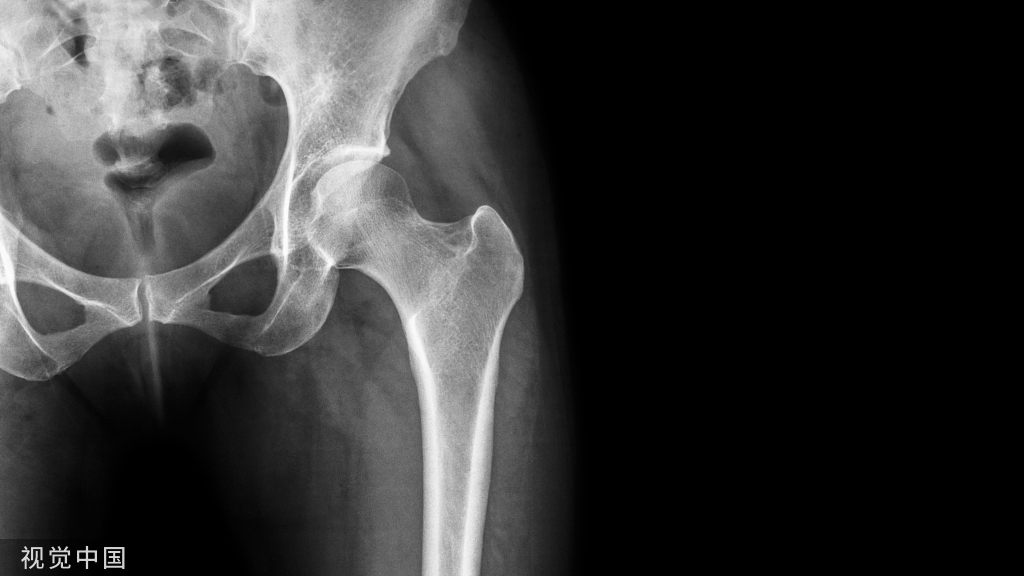

本次学习班讲师团队是来自河南省洛阳正骨医院(河南省骨科医院)郑州院区首席专家孙永强教授和兰州大学第二医院关节外科夏亚一教授,两位资深教授就髋膝关节置换标准化操作全程指导。

在通过理论授课、新鲜 cadaver 标本演示操作、手术视频讲解、手术直播、互动讨论的教学方式,全流程模拟手术场景,“从体表画线开始、入路解剖、髋臼侧处理、软组织平衡、股骨侧处理、术后功能锻炼指导”,系统、全面的学习髋膝关节置换的“标准化”的解剖入路及手术细节技巧,与会人员对人工关节置换术所遇到的问题、解决办法等问题进行了激烈讨论,孙永强教授和夏亚一教授纷阐述自己观点,分享自己手术经验,把学术推向高潮。